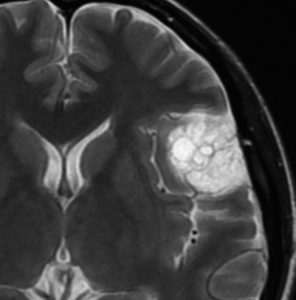

数年間経過観察されゆっくり増大したものです。多房性腫瘍です。

多くののう胞を含む髄膜腫です。実質部分では類円形の腫大核を有し核小体が明瞭な細胞がシート状に増生しています。細胞密度が高い部分がありますが,MIB-1染色率は2%程度です。WHO grade 1 microcystic meningiomaの像です。